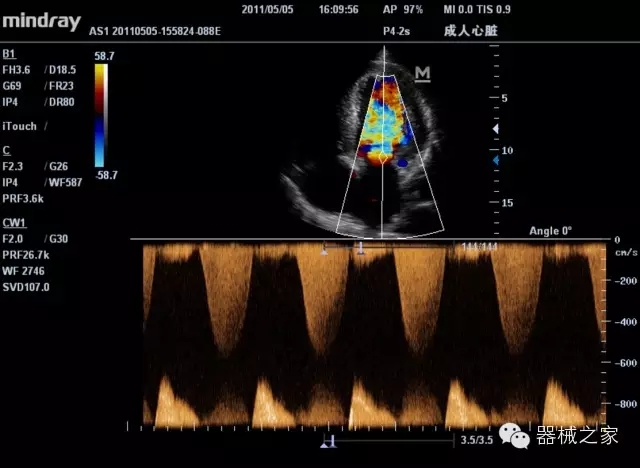

臨床圖片賞析

產(chǎn)品特點(diǎn)

·裝載有采用Multi-Core多核處理的非嵌入式平臺,成像效率大大提高,并且能夠給用戶帶來高速、多任務(wù)并行信號處理體驗(yàn);

·優(yōu)秀的圖像效果、強(qiáng)大的功能體驗(yàn)、豐富的探頭選擇、合理的便攜式設(shè)計,全中文顯示及病人管理界面,使得M7在任何場合、任何時候都能快速響應(yīng)更好的心血管、腹部、婦產(chǎn)、小器官等常規(guī)超聲檢查以及肌骨、神經(jīng)、顱腦、術(shù)中等新興領(lǐng)域的使用需求;

8倍波束并行處理系統(tǒng)

·在便攜式緊湊平臺上采用更多倍波束并行接收信號處理模式,無論二維還是彩色血流圖像狀態(tài)下,擁有更靈敏的回波頻移捕獲能力,大大提高時間分辨率,尤其使得心血管表現(xiàn)更為突出;

PSHI?寬帶頻移諧波技術(shù)

·在普通組織諧波的基礎(chǔ)上,通過精確控制的波束形成器,發(fā)射兩組具有相位偏差反向的信號,并采用并行信號處理,數(shù)字化合成并采樣回波信號,在高靈敏度的濾波器的處理過程中獲取更純凈的諧波信號,使圖像具有更加出眾的細(xì)節(jié)分辨率;